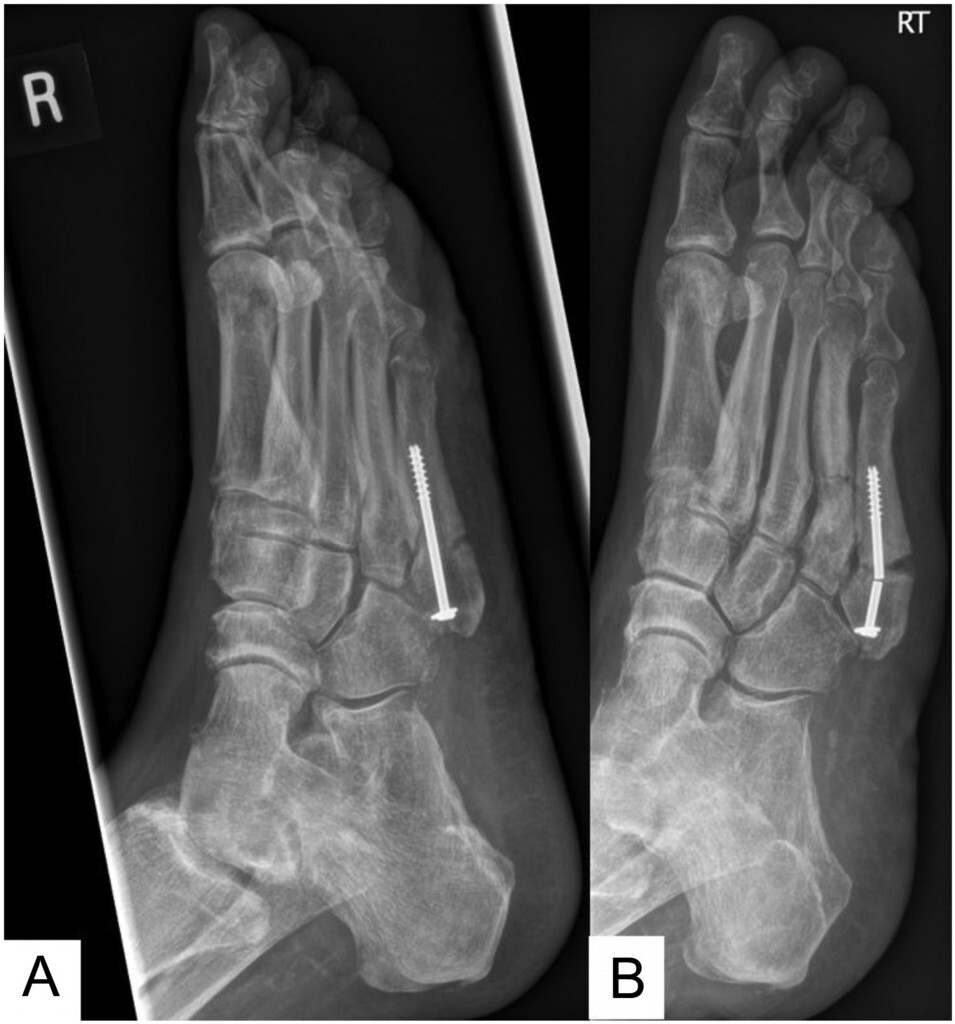

5th metatarsal bone fracture

talus fracture

navicular fracture

phalanges fracture

- 특히 허리 디스크로 발목거상이 안되는 환자가 무리하게 걸으면 발생하는 경우 있음.